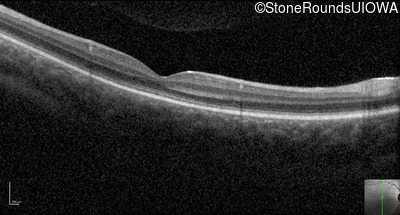

Optical Coherence Tomography - Right - 10/100

Exemplar / OCT Stack

Optical Coherence Tomography - Left - 10/100